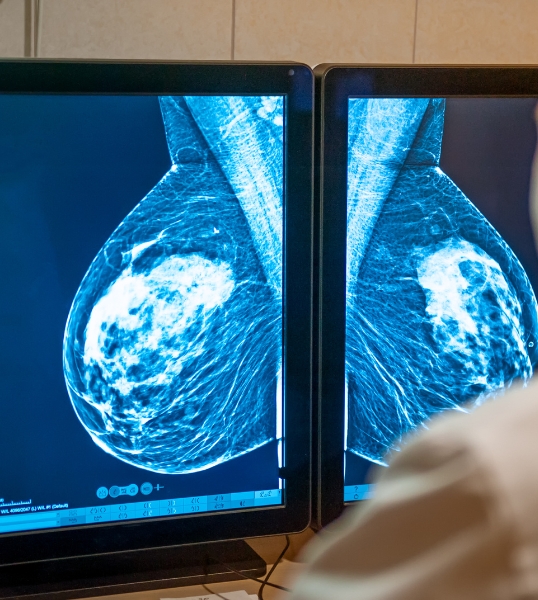

Chirurgie mammaire

• Chirurgie des nodules et tumeurs bénignes du sein

• Biopsies mammaires et surveillance post-opératoire